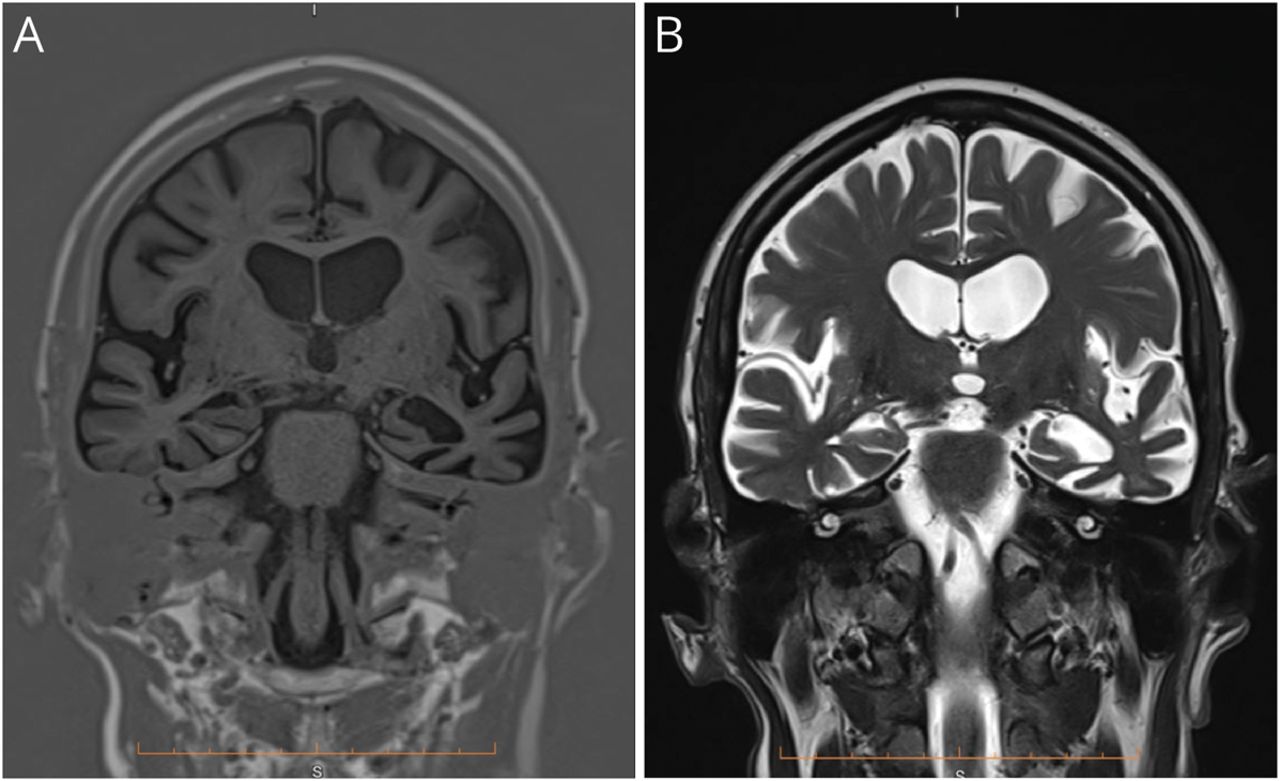

血清学的检测获得的代谢紊乱、维生素缺乏、感染、自身免疫,和多种的原因是noncontributory。大脑的核磁共振显示明显不对称左左前颞叶和海马和双边尾状萎缩。也有轻度到中度广义幕上的萎缩没有白质异常信号(图1)。

前颞叶所示冠状平面在t1 (A)和t2加权磁共振序列(B)。有不对称的左内侧颞叶萎缩与相应的侧脑室颞角增大。也有左额叶的体积损失的重要性在额叶和颞叶沟的空间。